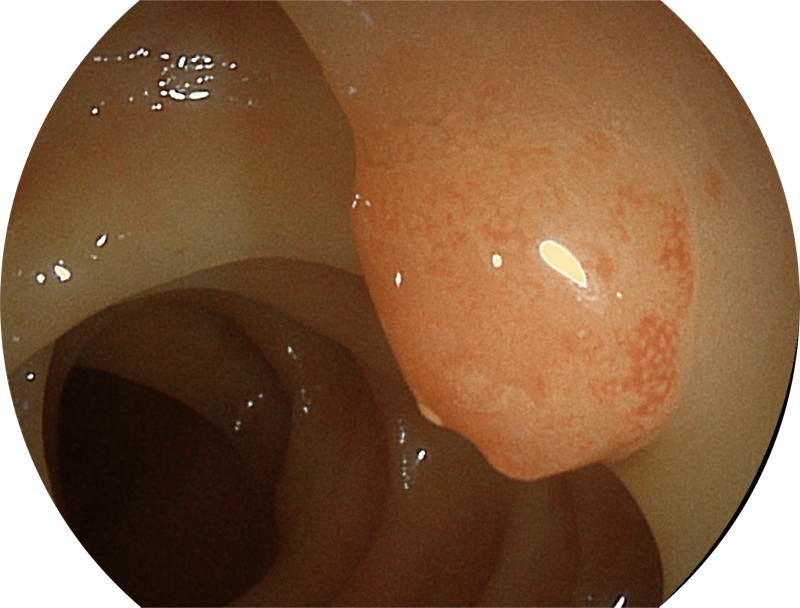

能够凸显黏膜浅层和中层血管轮廓,适用于中、远景观察下的病灶识别和早癌筛查。

能够凸显黏膜浅层血管轮廓和黏膜表面微结构,适用于中、近景观察下的早癌精确诊断。